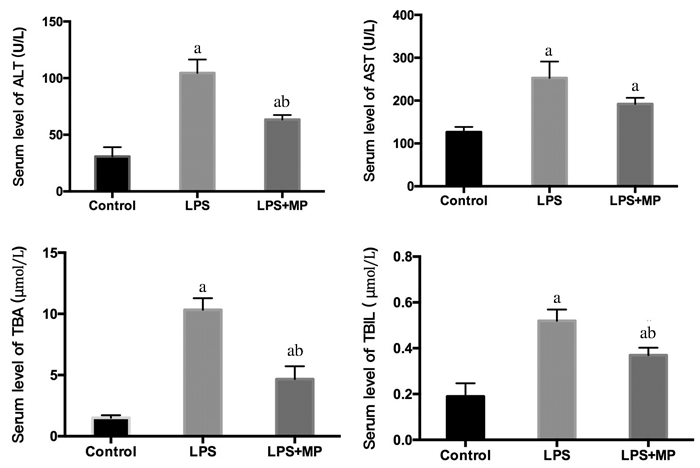

随着LPS处理时间的延长,小鼠血清ALT、AST、TBIL和TBA水平整体呈上升趋势(表 2)。腹腔注射LPS刺激48 h后,LPS组血清ALT、AST、TBIL和TBA水平(104.50±29.34 U/L,252.67±94.37 U/L,0.52±0.12 μmol/L,10.33±2.34 μmol/L)显著高于健康对照组(30.83±20.31 U/L, 126.60±29.48 U/L, 0.19±0.14 μmol/L, 1.50±0.55 μmol/L); LPS+MP组小鼠血清ALT、AST、TBIL和TBA水平(63.40±11.55 U/L,192.33±34.73 U/L,0.37±0.08 μmol/L,4.67±2.58 μmol/L)与正常组相比,差异有统计学意义(F=16.578,P < 0.01;F=5.620,P=0.016; F=11.120, P=0.002;F=28.995,P < 0.01);但与LPS组相比,LPS+MP组小鼠血清中只有ALT、TBIL、TBA水平显著降低(P=0.009; P=0.032; P < 0.01)(图 3)。

|

| 对照组、LPS组、MP干预组三组间血清ALT、AST、TBIL、TBA浓度比较,a表示与Control组(生理盐水组)比较P < 0.05;b表示与LPS组比较P < 0.05 图 3 小鼠血清肝功能相关指标变化(48 h) Figure 3 The changes of serum index of liver function |